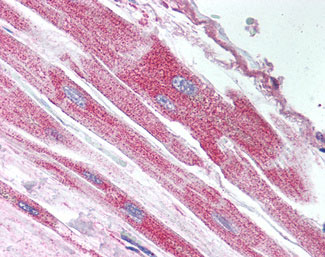

Anti-USP18 antibody IHC of human heart. |